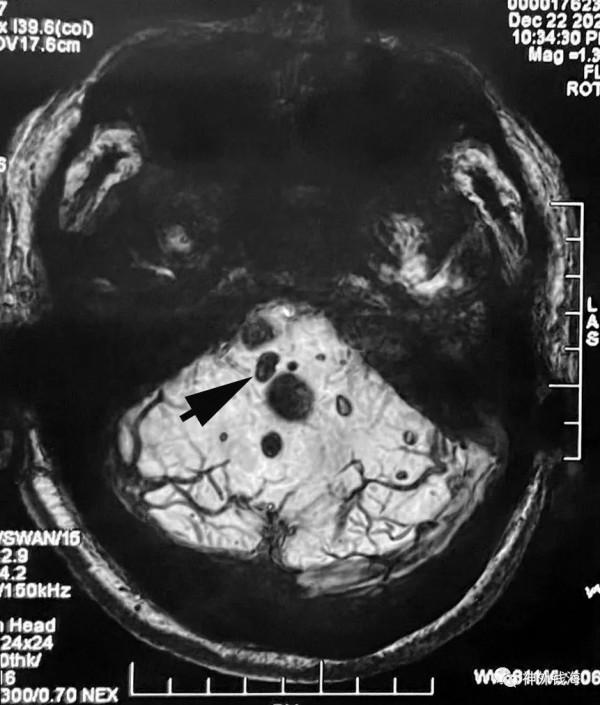

最後,讓我們看看在SWI(磁敏感成像)序列上第一個病灶的位置,以及其他微小病灶究竟有多少(無需處理,隨診即可,過度處理可能造成額外損傷)。

圖8 箭頭所示即為第一個被切掉的病灶。 其他星星點點還有不少微小病灶,暫時無需處理。